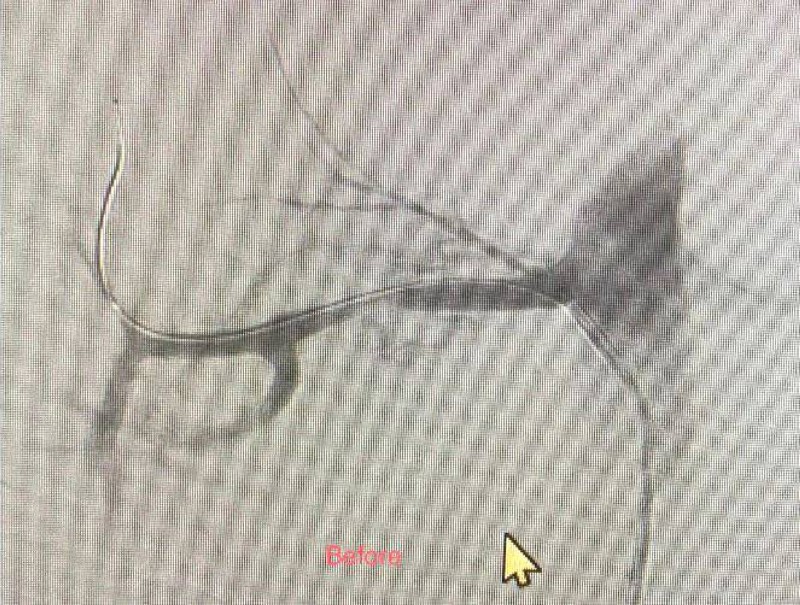

نجح فريق الأشعة التداخلية بمدينة الملك سعود الطبية من إنقاذ طفل (7 سنوات) ارتفع ضغط الدم الشرياني عبر علاجه بالأشعة التداخلية في حالة هي الأولى من نوعها بالمدينة. وكشف رئيس القسم الدكتور عزت باصهي أن خللا في التنسج العضلي الليفي أدى إلى تضييق الشرايين المغذية للكلى وقصور التروية الدموية لأنسجتها، وهي حالة نادرة من مسببات ارتفاع ضغط الدم، فيما تمكن الفريق من التدخل لتوسيع الشريان المغذي للكلية اليمنى عبر القسطرة والبالون الطبي، ما نتج عنه انخفاض مباشر في ضغط الدم، ووقف جميع الأدوية الخافضة للضغط. وغادر الطفل المدينة بعد 48 ساعة من الإجراء على أن تتم متابعته بشكل منتظم.